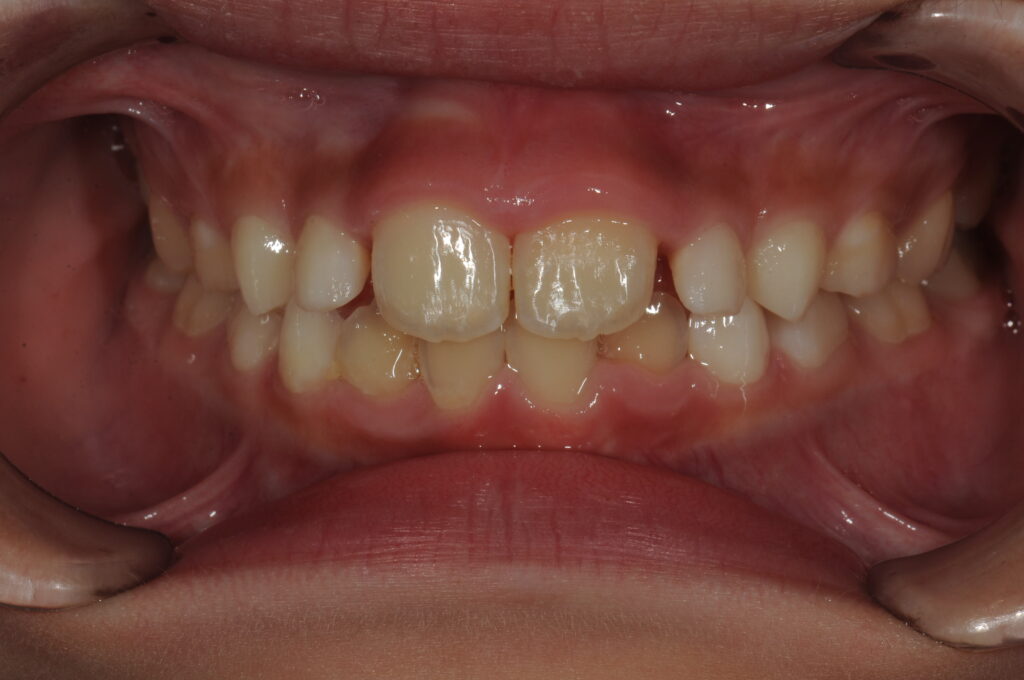

以下に術後の状態を示します。

【矯正治療後の状態】

いかがでしょうか。

また、治療期間はなんと1か月です!